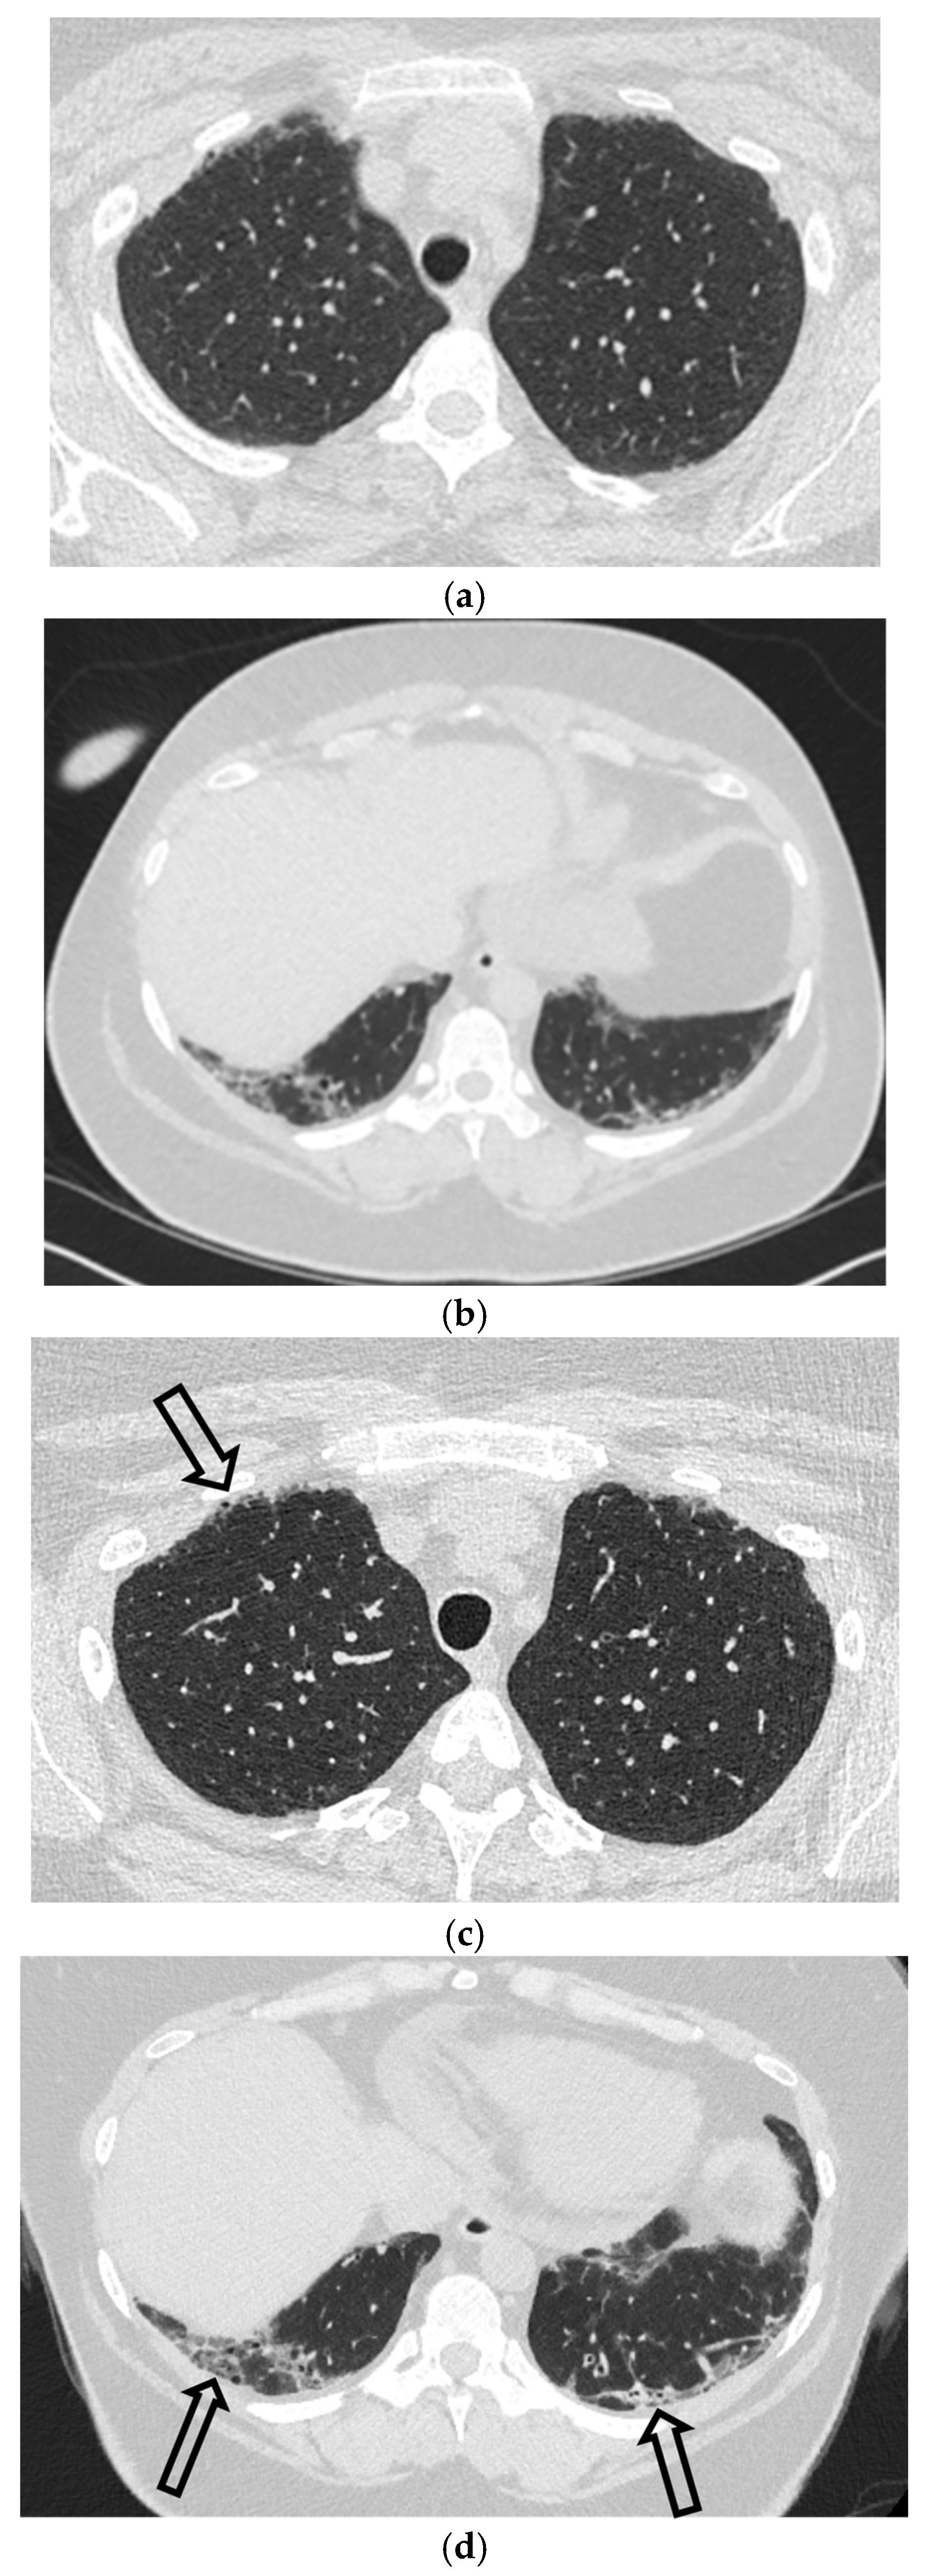

5.5. Diffuse Cystic Lung Diseases

5.5.1. Pulmonary Langerhans Cell Histiocytosis (PLCH)

5.5.2. Lymphangioleiomyomatosis (LAM)

5.5.3. Birt–Hogg–Dubé Syndrome (BHDS)

3.3. Computed Tomography (CT)